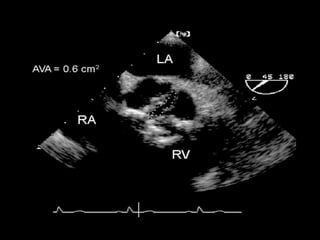

2D Echo-Long axis view

Diastole Systole

2D Echo-Long axisview Diastole Systole